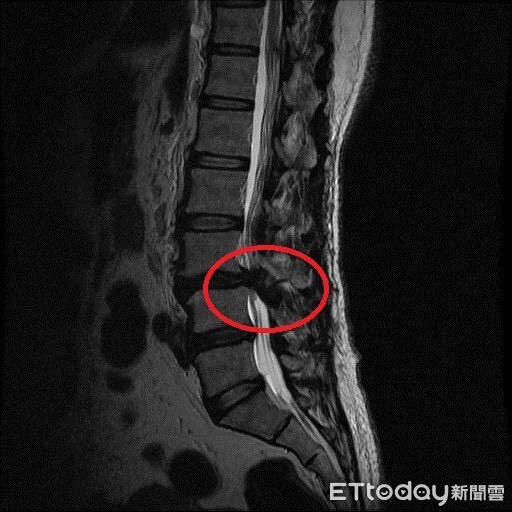

▲高女士的磁振造影顯示神經壓迫嚴重,經脊椎微創手術後第二天即可下床行走,花蓮慈濟醫院神經外科醫師吳聖文對吳女士説明復健衛教。(圖/花蓮慈濟醫院提供 下同)

「就是擔心脊椎手術後可能會癱瘓,拖累家人,所以就這樣一忍就是十多年。」遲遲不願接受手術治療的高女士,開始到處尋求食療偏方、推拿整脊等,沒想到越顯惡化,檢查後才知道問題出在腰椎第三、四節有椎間盤突出、滑脫、還合併嚴重椎管狹窄,由於神經缺損症狀嚴重,此時除了開刀減壓神經並固定外別無他法。

從影像學檢查發現,高女士的神經壓迫情況很嚴重,細細的神經柱就像被掐住一樣,加上高女士的腎功能差,幾乎只剩下健康人的十分之一左右時,更增加了手術的困難度。吳聖文醫師表示,脊椎微創手術的優點就是傷口小失血量少,不必破壞大量的肌肉和骨頭,在特殊工具和高倍率顯微鏡的幫助下,一樣可以做到神經完全減壓的效果,並儘量保有脊椎本身的骨性結構,最後再透過幾個一公分的小傷口將骨釘置入和固定,達成最後的融合過程。